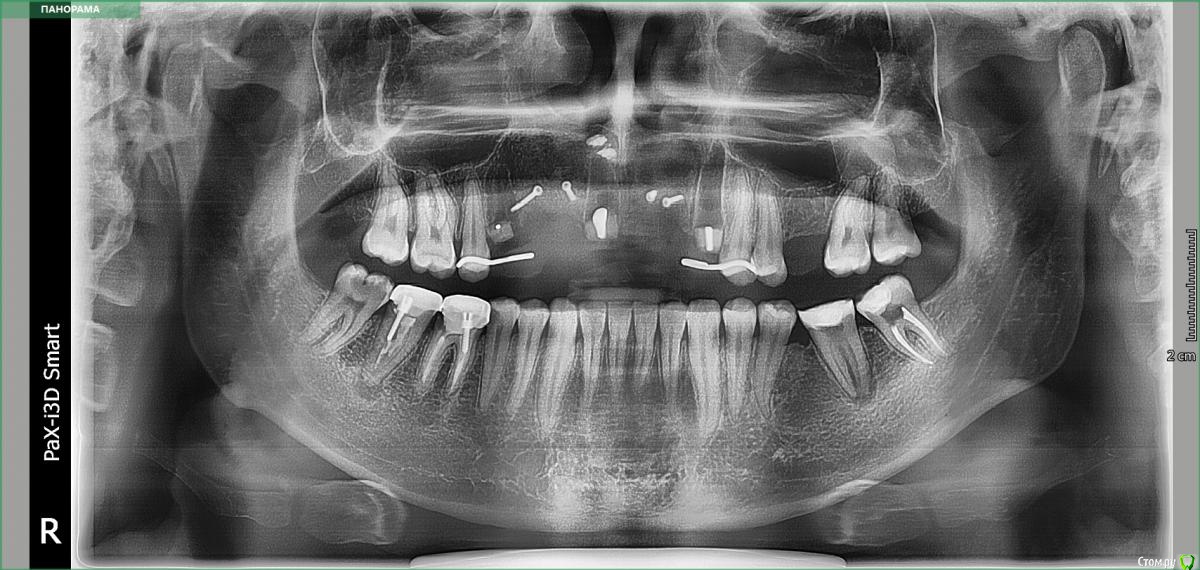

kamranchick Опубликовано 22 апреля, 2018 Поделиться Опубликовано 22 апреля, 2018 Камран, попробуй и узнаешь)))Дык у меня много работ таких на данный момент))) просто пока не раскрывал))))вот из последних) 3 Ссылка на комментарий

kamranchick Опубликовано 30 мая, 2018 Поделиться Опубликовано 30 мая, 2018 Реколы первые 1 Ссылка на комментарий